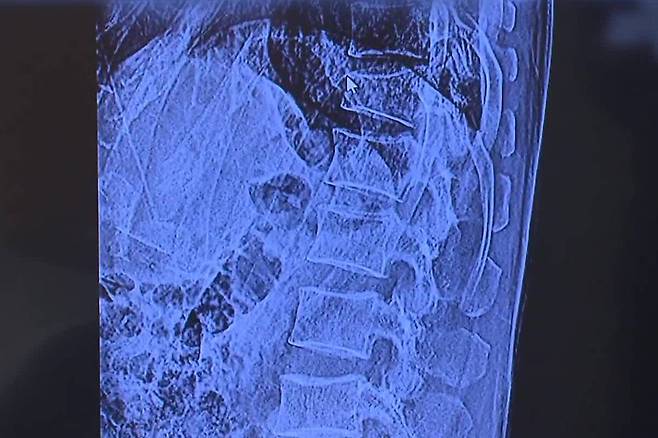

중국 산동중의학대 우페이 리 교수 연구팀은 커피와 차 소비가 골다공증 위험에 미치는 영향을 분석하기 위해 메타 연구를 진행한 것으로 알려졌다. 연구진은 2008년부터 2024년까지 발표된 관련 연구 중 14건을 선별하여 56만여 명의 데이터를 분석한 결과, 커피와 차는 각각 골다공증 위험을 21%와 25% 줄인다는 연구 결과가 나왔다고 밝혔다.

실제로 연구에 따르면 커피는 하루 한 잔 이상, 차는 일주일에 네 번 이상 섭취했을 때 이러한 효과가 두드러졌다. 연구팀은 카페인의 적당량이 파골세포(뼈를 파괴하는 세포)의 활동을 억제하며 커피 속 플라보노이드와 칼륨 성분이 뼈 건강에 이바지한 것으로 보인다고 설명했다.

이어 차의 경우 폴리페놀 성분이 뼈 미세 구조를 개선하고 뼈 밀도를 높인 것으로 분석됐다. 또한, 이러한 결과는 국내에서도 등장했다.

실제로 서울대병원 가정의학과 박상민 교수팀이 폐경 여성 4,066명을 대상으로 연구를 진행한 결과, 하루 한 잔 이상 커피를 섭취한 여성의 경우 골다공증 위험이 최대 35% 감소한 것으로 나타났다. 특히 하루 세 잔 미만의 커피 섭취가 가장 효과적이었던 것으로 파악됐다.